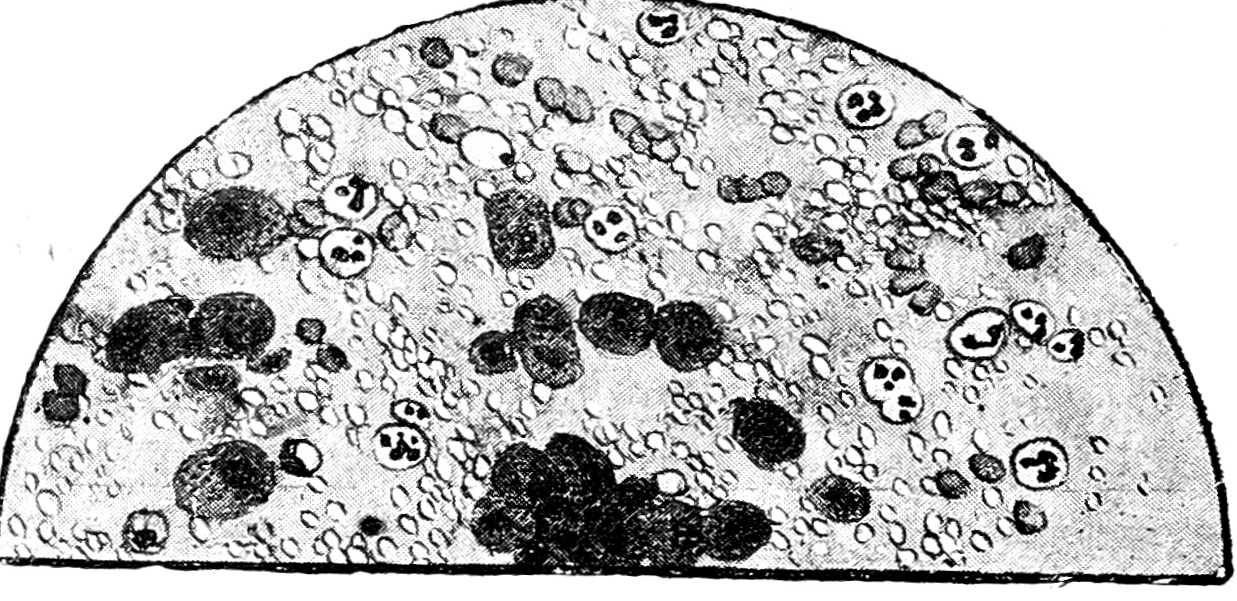

Рис. 6. Абсцесс легкого. Фон грязный, очень много ядер дегенерированных N, бронхиального и альвеолярного эпителия.

Рис. 8. Tbc pulmonum открытый, доброкачественно протекающий. Слизистый фон, много МП, AM, N, все формы перехода МП в AM.

Рис. 9. Tbc pulmonum открытый, недоброкачественного течения. Фон грязно-серый, дегенерированные N, ядер много, небольшое количество МП, редкие AM.